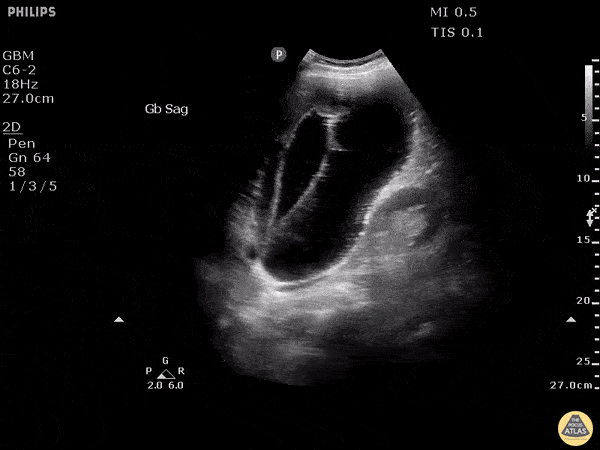

Biliary - Gangrenous Cholecystitis

Stone trapped in cystic duct resulted in gallbladder distention as well as sloughing of intraluminal membranes. Image courtesy of Robert Jones DO, FACEP @RJonesSonoEM Director, Emergency Ultrasound; MetroHealth Medical Center; Professor, Case Western Reserve Medical School, Cleveland, OH View his original post here